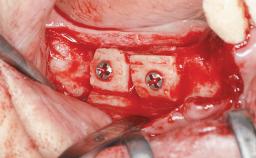

Iliac and Calvarial Bone Blocks for Onlay Grafting of a Severely Resorbed Edentulous Maxilla

A 45-year-old woman with a completely edentulous maxilla was referred to evaluate the possibility of rehabilitation with an implant-supported prosthesis. This patient was healthy and a non-smoker. She had been wearing a maxillary complete denture opposing a natural mandibular dentition since her twenties. This situation had resulted in progressive resorption of the alveolar ridge, repeatedly creating a need for relining the denture. Twenty years later, despite multiple adaptations and the use of “glues” the denture was unstable and causing the patient psychological and functional discomfort.

| Bone Augmentation | Horizontal|Sinus Floor Elevation|Staged|Vertical |

| Augmentation Materials | Autogenous chips|Autogenous block(s) |

| Bone Volume | Deficient vertically or deficient vertically AND horizontally |